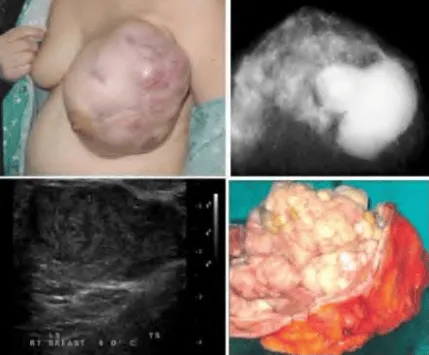

Phần tiêu đề “Cận lâm sàng”Hình ảnh “Bướu diệp thể: Khối lớn, rõ, có các vùng hóa nang và thùy. Nhũ ảnh cho thấy vôi hóa không đồng nhất, siêu âm thể hiện khe rãnh và hóa nang”.

Siêu âm:

- Khối giảm âm, bờ rõ, có thể có các vùng hóa nang (cystic spaces) phân bố rải rác.

- Gợi ý phẫu thuật ngay nếu khối lớn, tăng sinh mạch máu bất thường.

Nhũ ảnh: Khối lớn, giới hạn rõ, có thể bầu dục, hình tròn hoặc chia thùy, thỉnh thoảng thấy vôi hóa (ít phổ biến hơn fibroadenoma).

MRI: Thần kinh hóa mô đệm rõ, khối đồng nhất hoặc có vùng thoái hóa, bắt thuốc mạnh - thường dùng trong khối nghi ngờ ác tính hoặc khối tái phát.